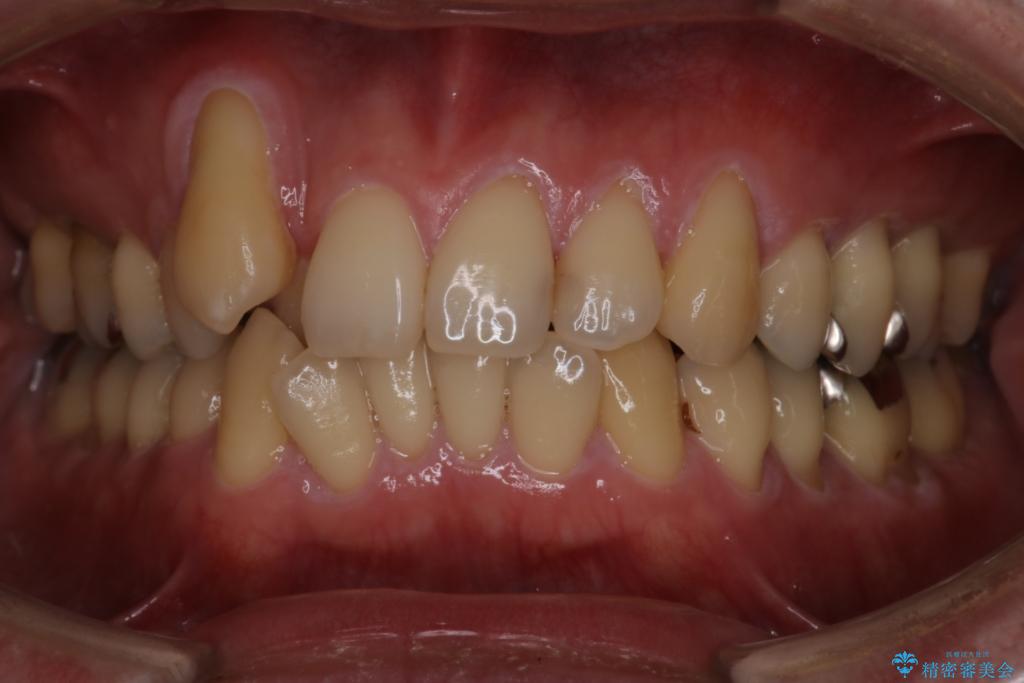

抜歯の本数を最小限に抑えたことで、治療計画も1年5ヶ月と短期間で終了することができ

主訴である前歯のがたつきも改善され綺麗な歯並びになりました。

矯正の装置を除去したタイミングで、ホワイトニングも行うことで歯の色味も白くなりました。